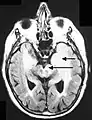

- Imagen de RM en secuencia FLAIR que demuestra infiltración relacionada con tumor que involucra núcleos lenticulares (Flecha).

- Imagen de RM en secuencia FLAIR que demuestra la infiltración relacionada con el tumor que afecta tanto a los lóbulos temporales (flecha corta) como a la sustancia negra (flecha larga).